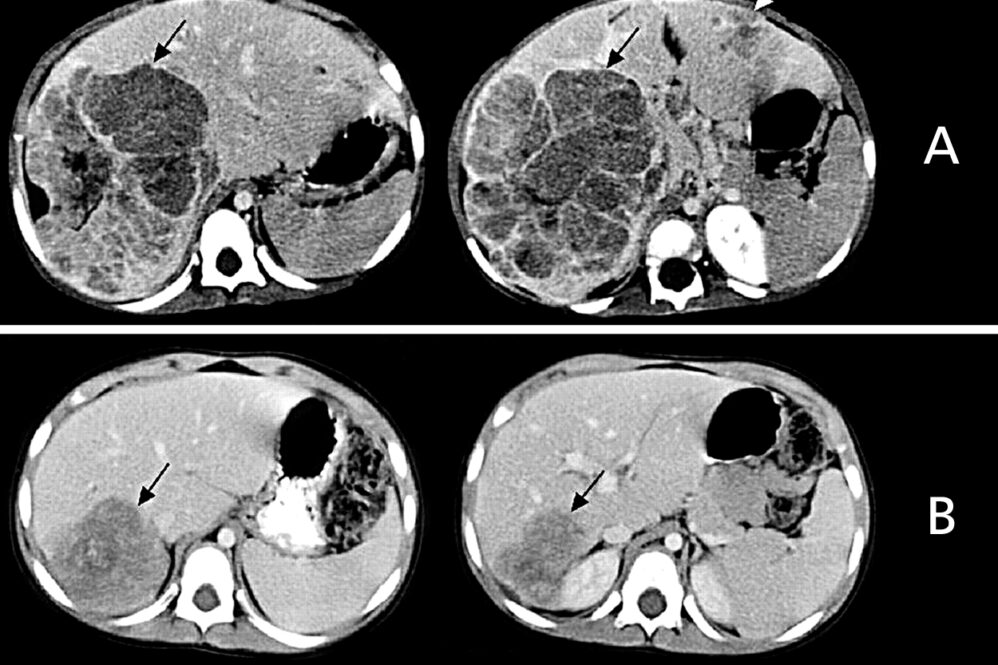

Η διάγνωση τίθεται με το US και επιβεβαιώνεται με την ΑΤ και τη MRI, με τις οποίες σχεδιάζεται το πλάνο της χειρουργικής θεραπείας, όπως και για κάθε όγκο του ήπατος. Πρέπει να τονισθεί ότι ο όγκος είναι σχετικά ανάγγειος (Εικόνα 1).